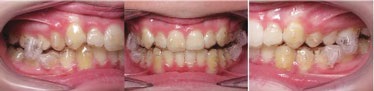

Fig. 6: Three-month progress records, with weekly aligner changes.

Fig. 7: Six-month progress records, with weekly aligner changes. Class I molar and canine relationship was achieved, but the transverse and posterior vertical dimensions still needed correction.

Fig. 8: End of mandibular advancement phase, with weekly aligner changes for 12 months. (Upper and lower: 23, then 26, each.)